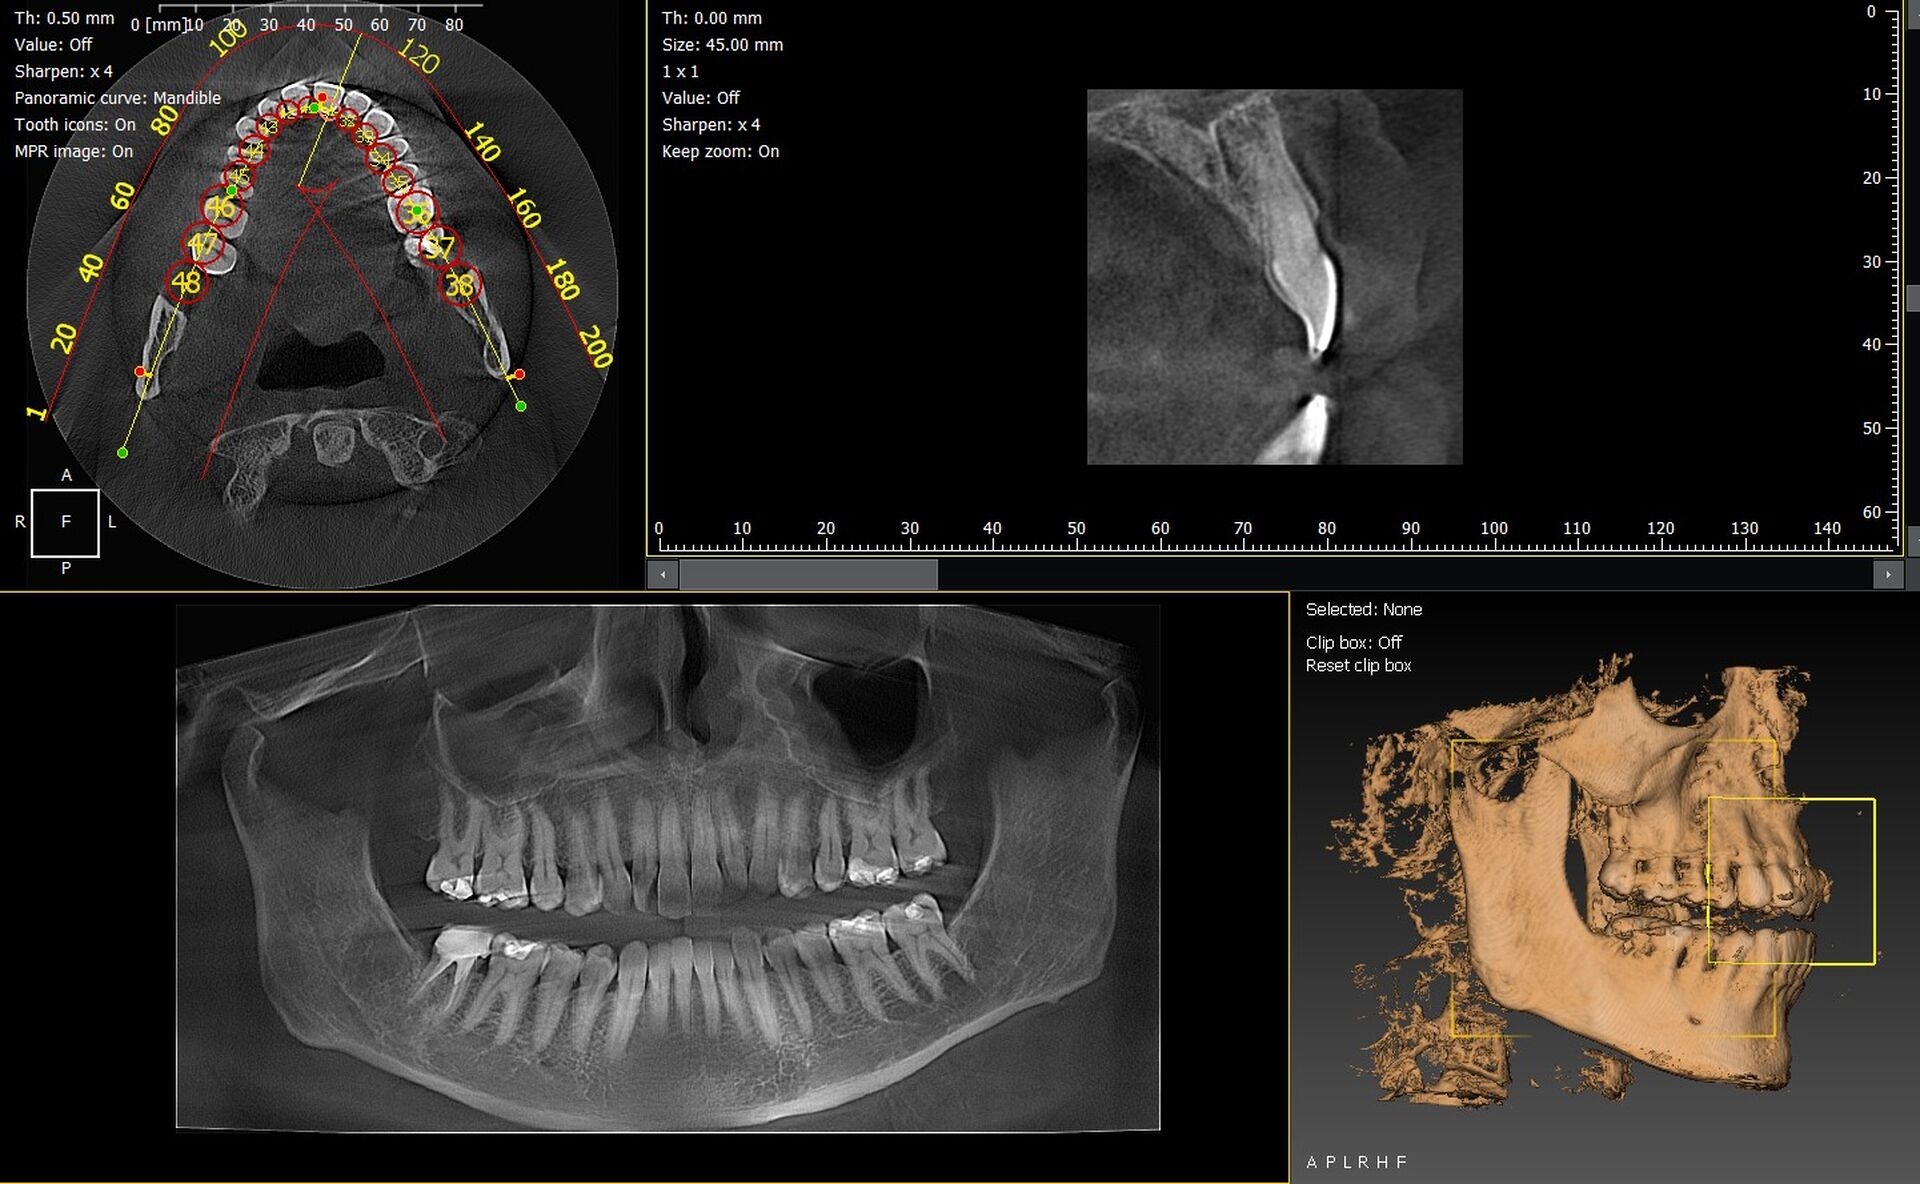

L’I-Max 3D XPRO est un système Cone Beam multifonction 4-en-1 conçu pour fournir une imagerie dentaire ultra-précise dans divers modes : panoramique, 3D, céphalométrie et scan d’objets (modèles en plâtre, porte-empreintes).

La qualité d’image est exceptionnelle, avec une résolution de 70 microns, assurant une finesse diagnostique accrue.

Le champ d’imagerie (FOV) peut être ajusté entre 16×11 cm à 5×5 cm, ce qui permet de cibler précisément la zone d’intérêt et de limiter l’exposition aux rayonnements.

La technologie Super IGZO est au cœur de ce système, avec des innovations telles que le traitement IA (algorithmes de débruitage), le Focus Scintillator pour réduire le bruit et l’algorithme AutoMAR pour atténuer les artéfacts métalliques.  Le positionnement "face à face" améliore le confort du patient et la reproductibilité des prises de vue.

Grâce à sa compacité (empreinte au sol inférieure à 1 m²) et son installation murale ou en colonne, l’appareil peut s’adapter aux contraintes d’espace des cabinets.  L’interface est intuitive, facilitant le passage entre les modes 2D et 3D, et la planification implantaire est supportée par le logiciel QuickVision 3D intégré pour visualiser, simuler et guider les interventions.